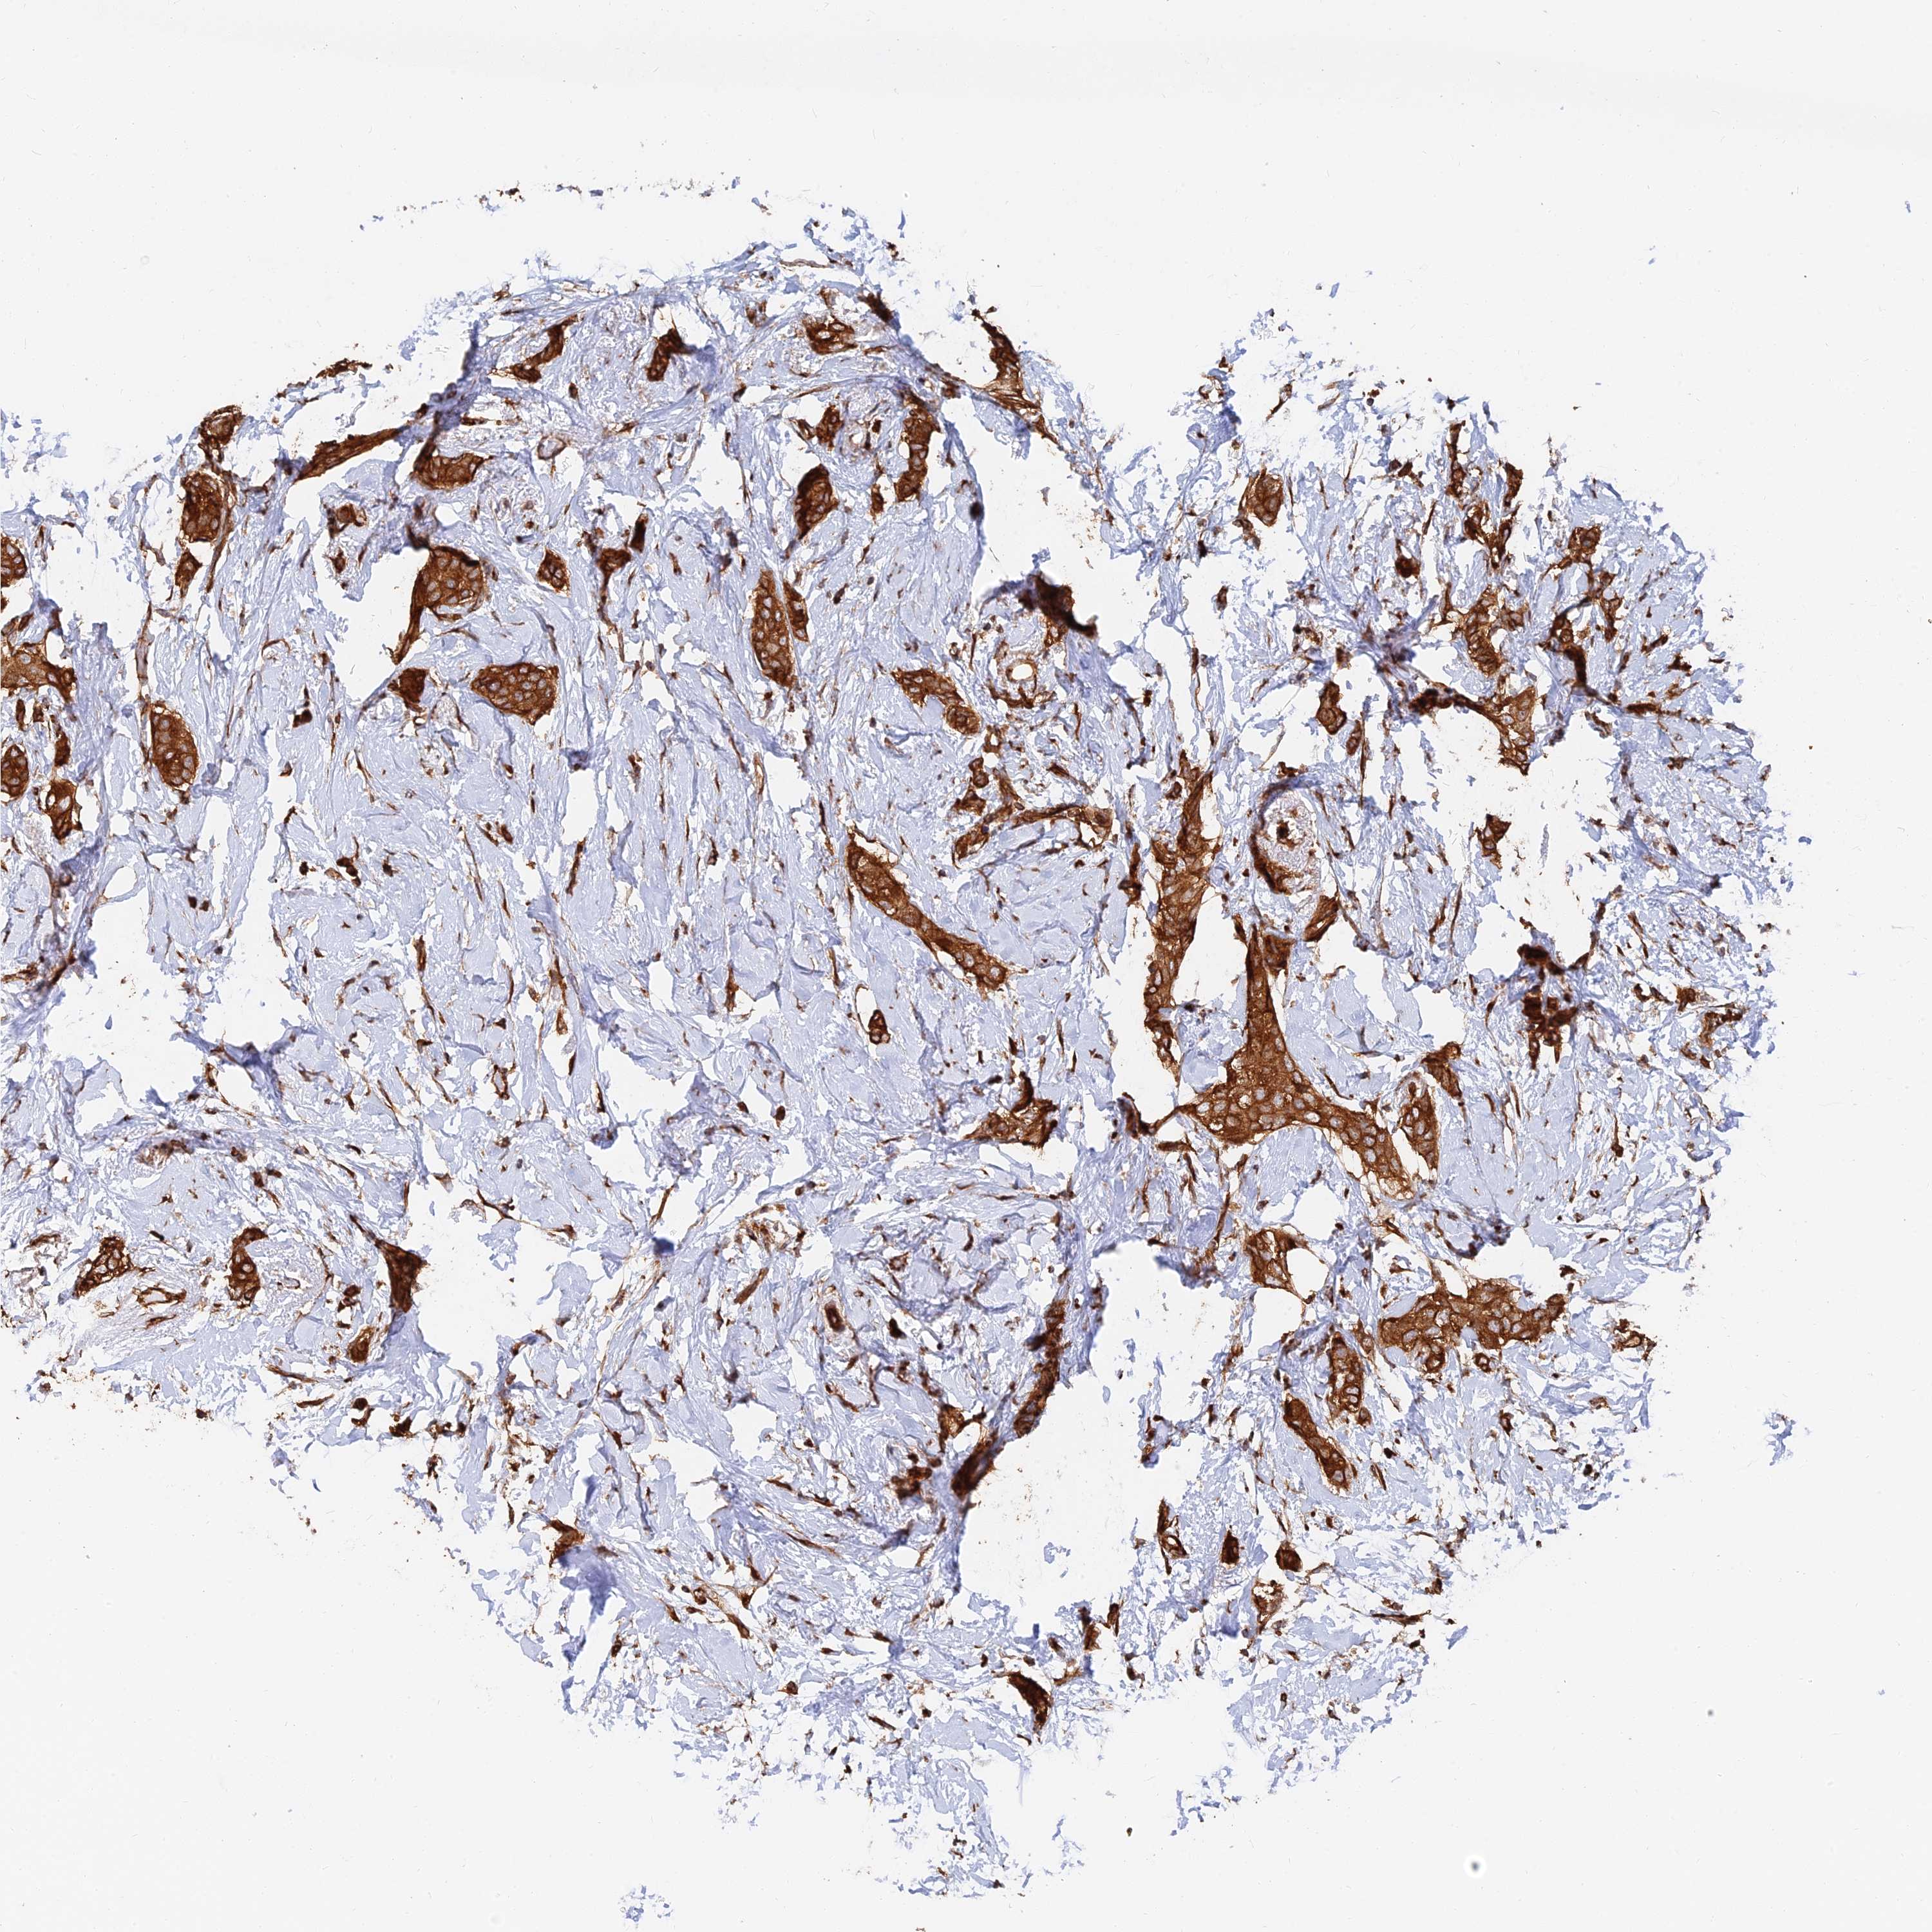

BRCA TCGA BRCA VALIDATION PROTEIN EXPRESSION

ANTIBODIES

AND

VALIDATION